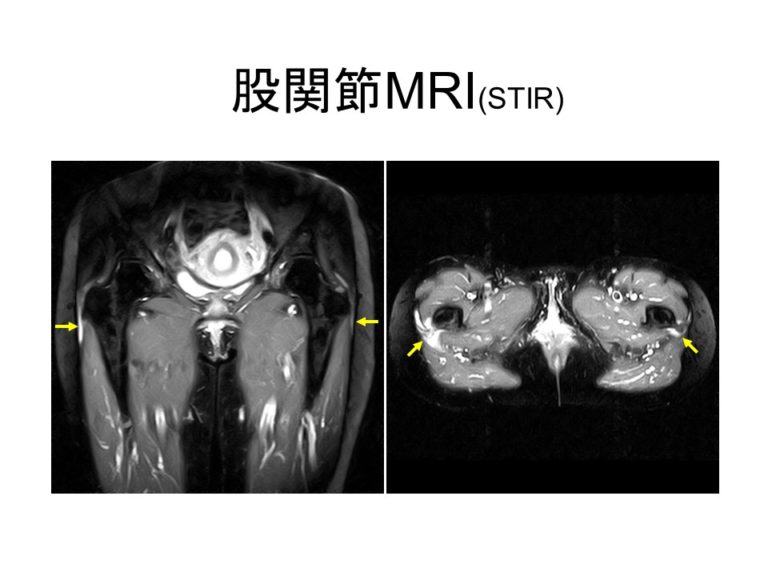

リウマチ性多発筋痛症は, 巨細胞性動脈炎 (側頭動脈炎)と密接に関連する症候群である。 55歳以上の成人に発生する。 典型的には近位筋に重度の痛みおよびこわばりが生じ(筋力低下や萎縮は伴わない),非特異的な全身症状を呈する。. リウマチ性多発筋痛症(polymyalgia rheumatica: PMR)は、50歳以上の年齢の方に多く発症し、肩の痛み、体に近い側の肩や上腕、大腿などの四肢近位筋主体の痛みや朝のこわばりと、微熱、倦怠感を呈する炎症性疾患です。. 男女比は1:2~3で女性に多く、発症年齢.